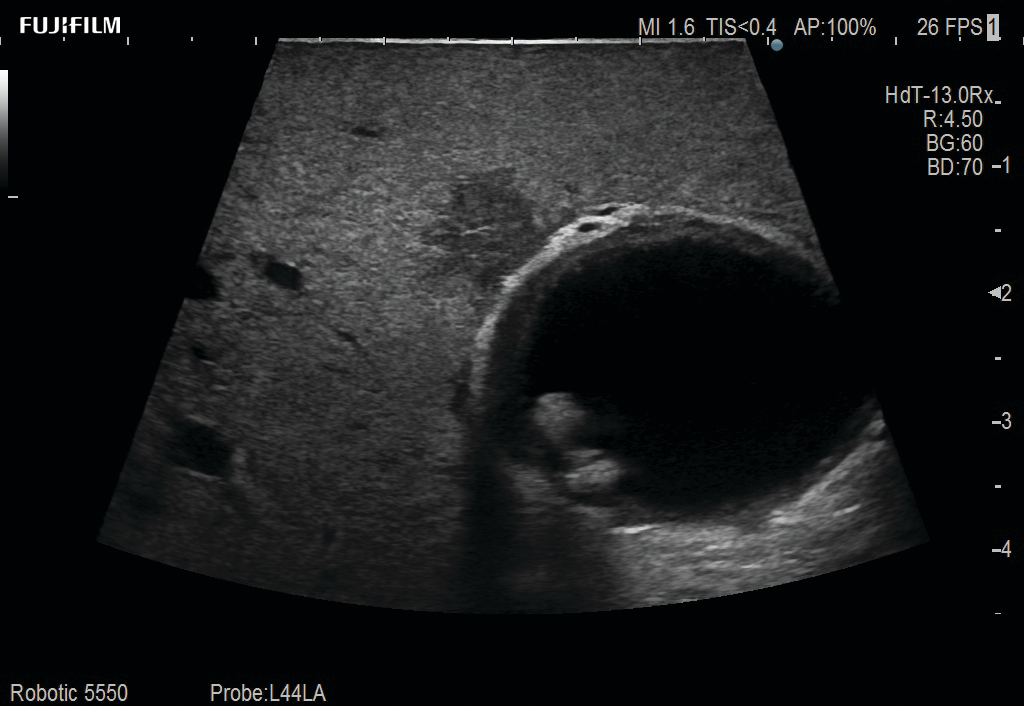

Laparoscopic Cholecystectomy and Hepatectomy using L44LA

Exclusive linear array 4-way laparoscopic transducer for better visualization of targeted lesions.